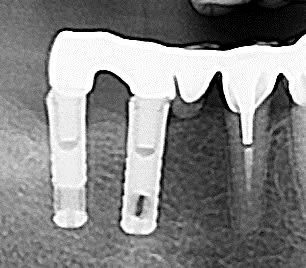

Et une autre pano

En effet ça ressemble terriblement à un steri-oss flat top ou un THD

je me disais bien que ce design de spire je l'avais déjà vu quelque part...

IMZ twinplus